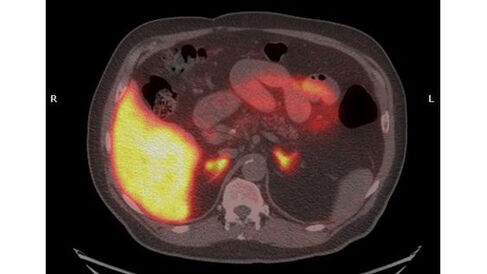

Professor Franklin Aigbirhio works in the Wolfson Brain Imaging Centre. His group investigates the development and application of molecular imaging probes, in particular for the in vivo imaging technique Positron Emission Tomography (PET). PET scanning is widely used for imaging tumours and for clinical diagnosis of certain brain diseases such as those causing various types of dementia. The technique depends on detection of gamma rays emitted by a radionuclide tracer, which is introduced to the body on a biologically active molecule. Designing probes that will target the precise area of the brain or other organ that the clinician wishes to image is challenging.

Aigbirhio's reserach objectives are to design, develop and apply imaging probes that are specific and selective to biological markers and are sensitive to biochemical changes associated with disease mechanisms. In 2016, in collaboration with other researchers at Cambridge and Uppsala University Sweden, he decided to apply for a grant from the MRC’s Biomedical Catalyst: Developmental Pathway Funding Scheme (DPFS) to develop and trial a particular molecular probe for PET imaging of the adrenal gland. The aim is to improve diagnosis and inform treatment of PHA, thus addressing a significant unmet need.

Image: PET-CT scan of adrenal glands using the radiopharmaceutical [11C]Metomidate. (Courtesy of Franklin Aigbirhio, Morris Brown Mark Gurnell)